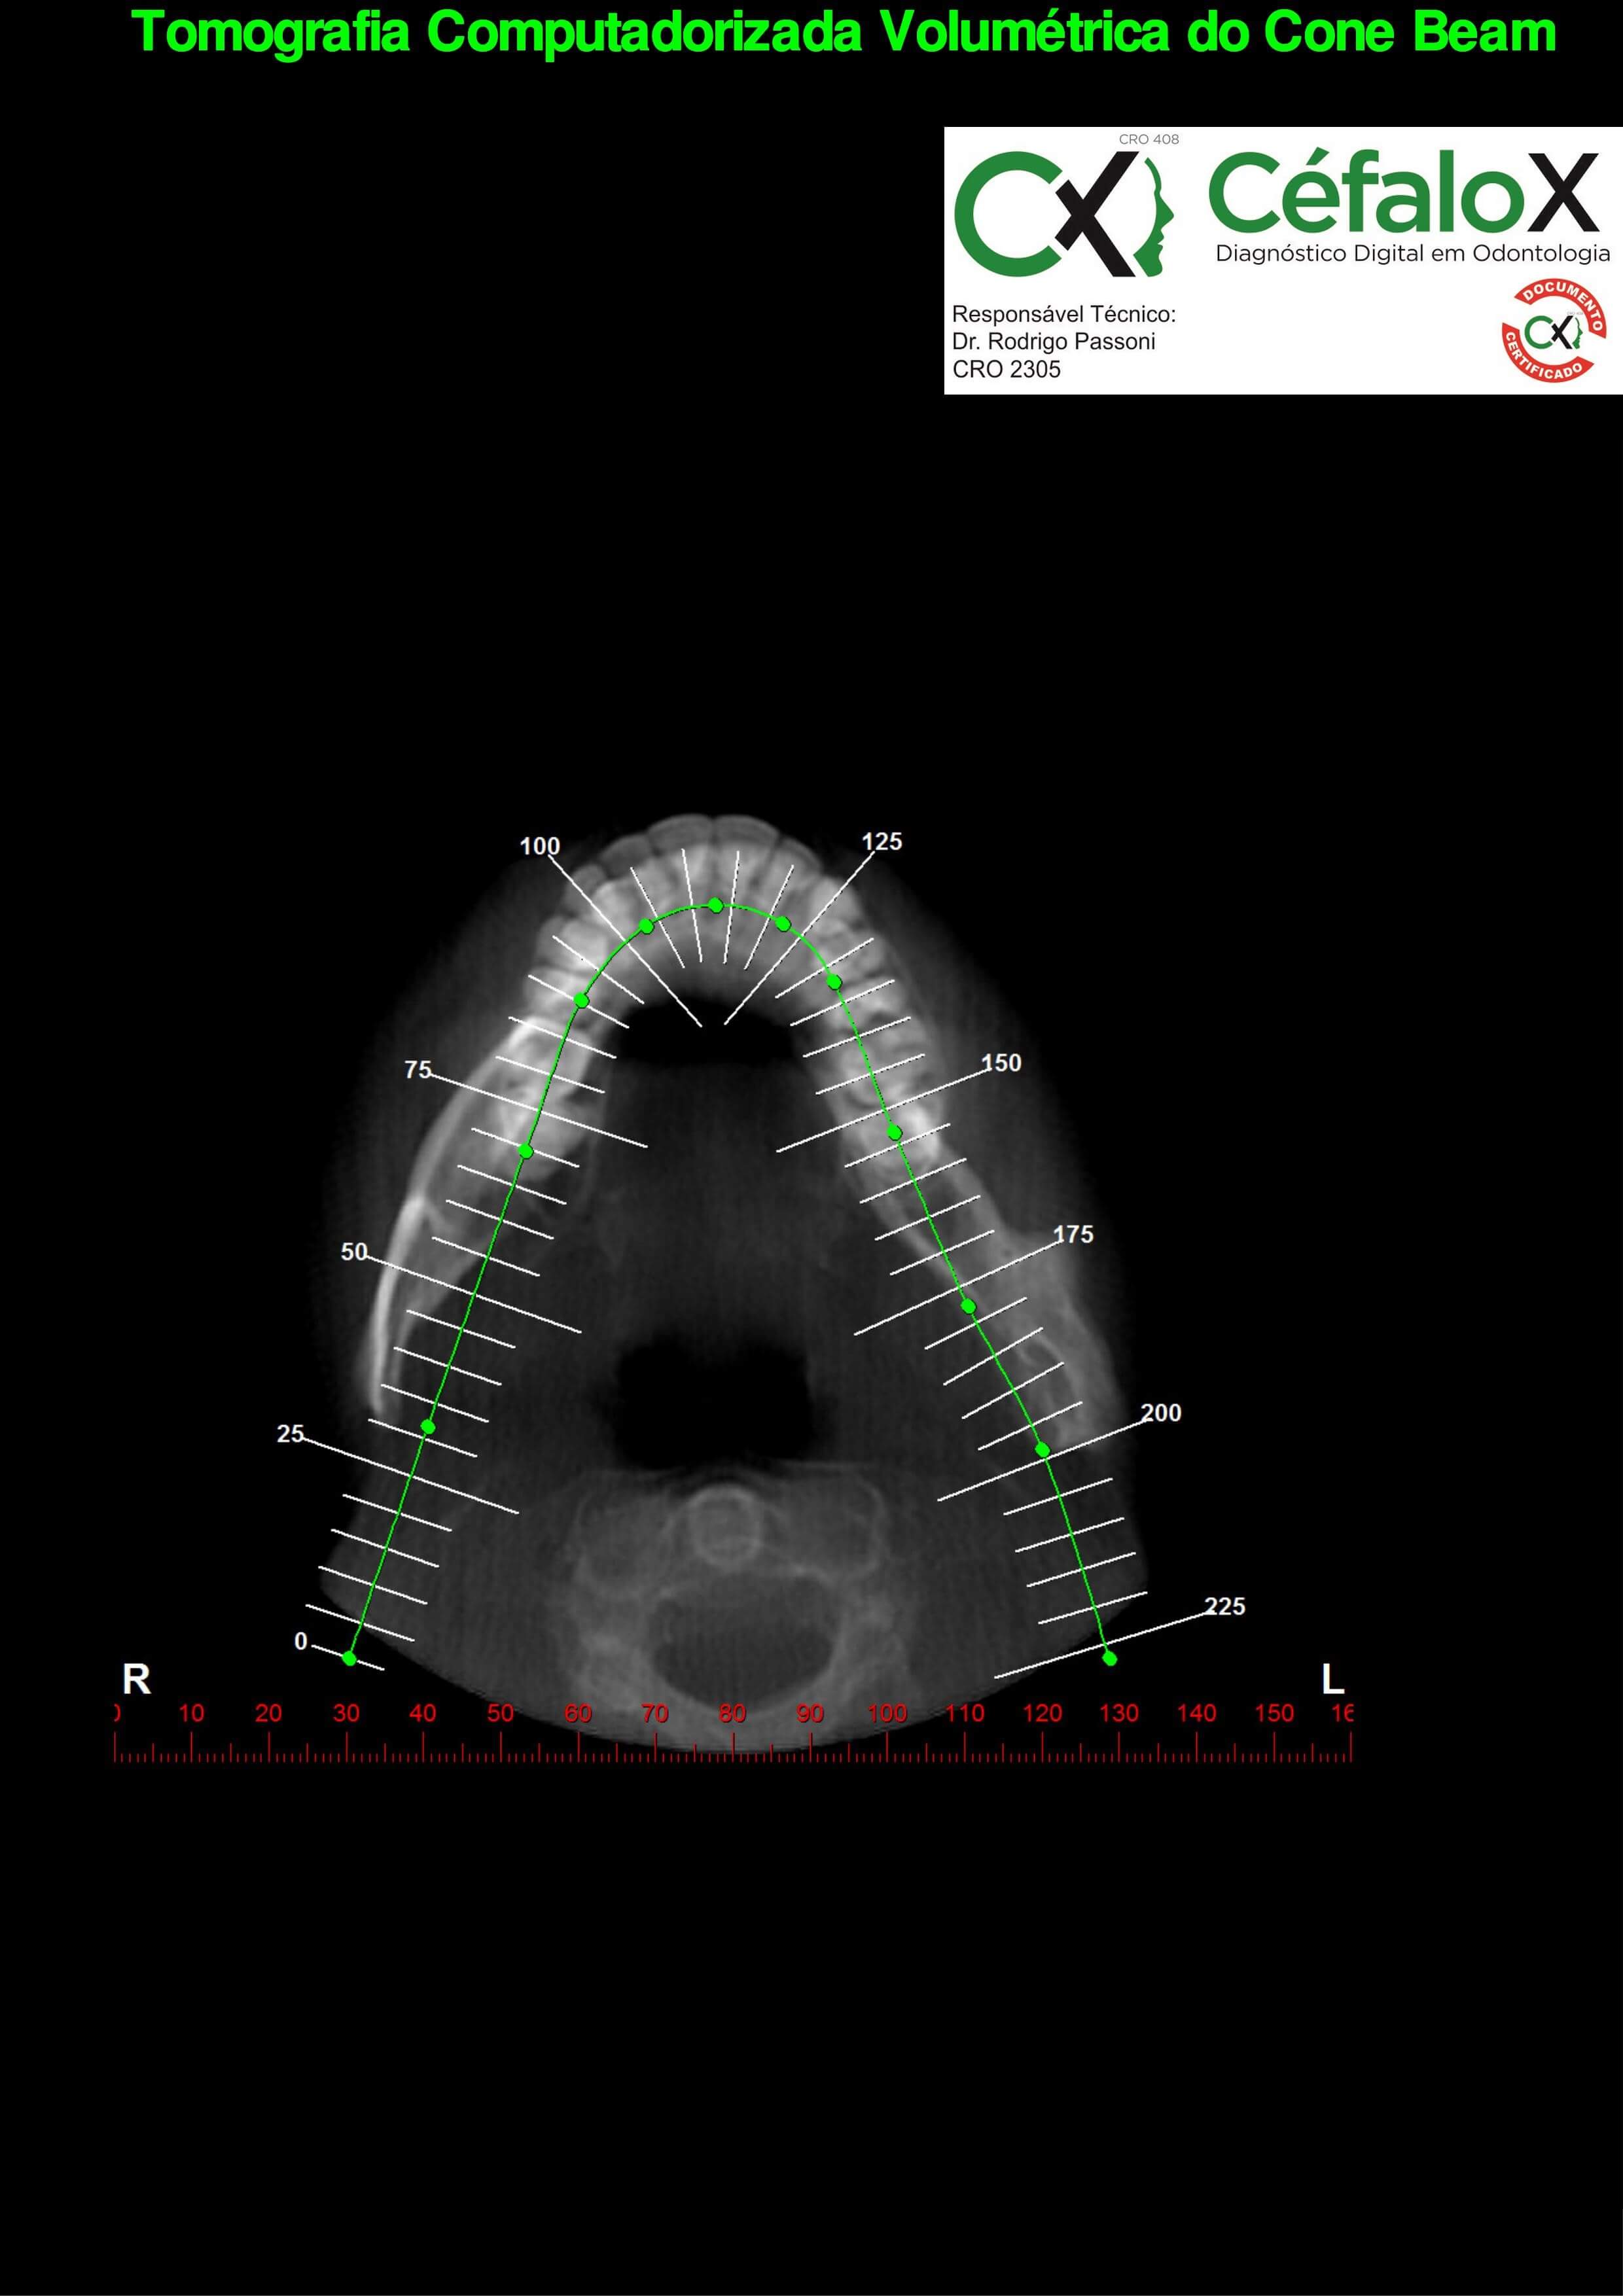

TC de face (do Hióide à Glabela), reconstrução 3D do tecido ósseo, radiografia panorâmica, telerradiografia lateral com traçado, cortes transversais e axial de maxila e mandíbula e arquivo DICOM- entregue em pasta de Pvc.

TC de face (do Hióide à Glabela), reconstrução 3D do tecido ósseo, radiografia panorâmica, telerradiografia lateral e frontal com traçado, cortes transversais e axial de maxila/mandíbula e arquivo DICOM – entregue em pasta de Pvc.

TC de face (do Hióide à Glabela), reconstruções 3D do tecido mole/ósseo/vias aéreas, radiografia panorâmica, telerradiografia lateral e frontal com traçado, cortes transversais e axial de maxila/mandíbula, ATM e arquivo DICOM – entregue em pasta e caixa de Pvc.